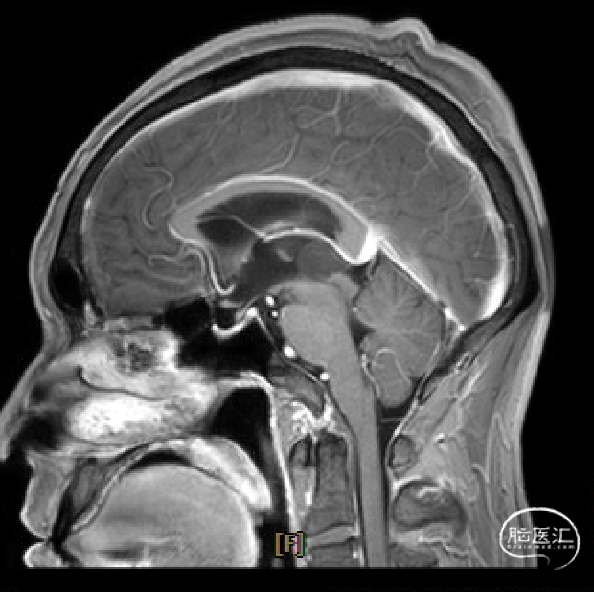

患者5年前无明显诱因出现阵发性头晕,无明显头痛、恶心呕吐等不适,开始未予重视,2022-7-19出现头晕加重,伴视力下降,遂于2022-7-24在当地医院行颅脑MRI提示:松果体区肿瘤伴梗阻性脑积水。

手术方式

术后复查

术区无出血,脑室系统较术前显著缩小,脑积水缓解。

术前MRI与术后复查MRI对比